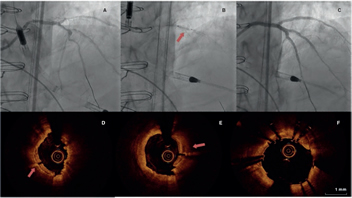

Regarding the procedure, it should be noted that the crossing rate for the ICL balloon was 100% despite a high percentage of plaque preparation was required (62% balloon pre-dilatation, 27% rotational atherectomy). Recently, the combination of rotational atherectomy and ICL has been described as RotaTripsy, suggestive that these 2 calcium debulking techniques may be complementary, since rotational atherectomy facilitates the ICL balloon crossing, and the latter facilitates proper expansion in the presence of circumferential deep calcium plaques.9 The device success rate was 84% (100% in the Disrupt CAD II linical trial) and the clinical success rate was 95% (94% in the Disrupt CAD II trial). And most important of all, no major procedural complications were seen, which is consistent with the Disrupt CAD II trial results. The rupture of the ICL balloon during inflation occurred in 3 cases (12%) without associated complications, yet the rupture of the balloon has been described in a case report resulting in a type C coronary dissection; the interventional cardiologist needs to be aware of this lithotripsy-related potential complication.10 Intravascular imaging were performed in few cases probably because the operator thought it would be difficult to cross an especially severe and calcified lesion with the OCT or IVUS catheter. Consistent with the results of the Disrupt CAD I and II clinical trials and OCT substudy,5,11 it was confirmed that the modification of calcium and the presence of fractures lead to an acute area gain and favorable stent expansion in the lesions assessed through OCT in our series. Figure 1 shows the coronary angiography and OCT of one complex patient treated with ICL; the red arrows seen on figure 1D,E indicate calcium fractures after the ICL.

Figure 1. Intracoronary lithotripsy, angiography, and optical coherence tomography. Patient with severe coronary artery heart disease with severely depressed left ventricular ejection fraction previously treated with coronary artery bypass graft (venous graft-left anterior descending coronary artery, currently occluded). Treatment of left main coronary artery, left anterior descending artery, and diagonal branches. A: pre-intracoronary lithotripsy angiography. B: Impella-assisted PCI of left anterior descending coronary artery. Arrow indicates inflated lithotripsy balloon. C: successful final angiographic result after stenting. D, E and F: optical coherence tomography cross-sectional images of a post-lithotripsy calcified lesion. Red arrows indicate calcium microfractures after intracoronary lithotripsy.